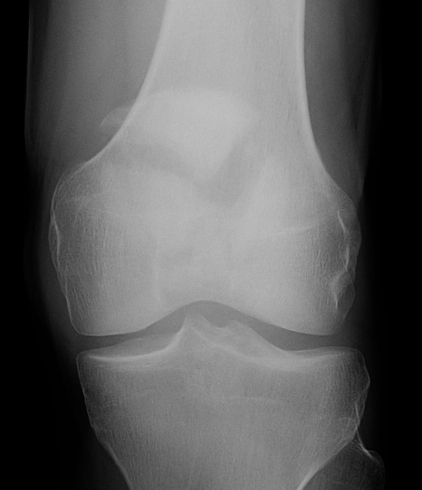

4. Patellectomy

Technique

Concept

Excise patella in full close retinaculum tightly with VMO advancement

Concerns

- extensor lag and weakness

- continued pain if trochlea lesions

- issues with later TKA

Indications

- unreconstructable fracture

Risks

- extension lag / weakness